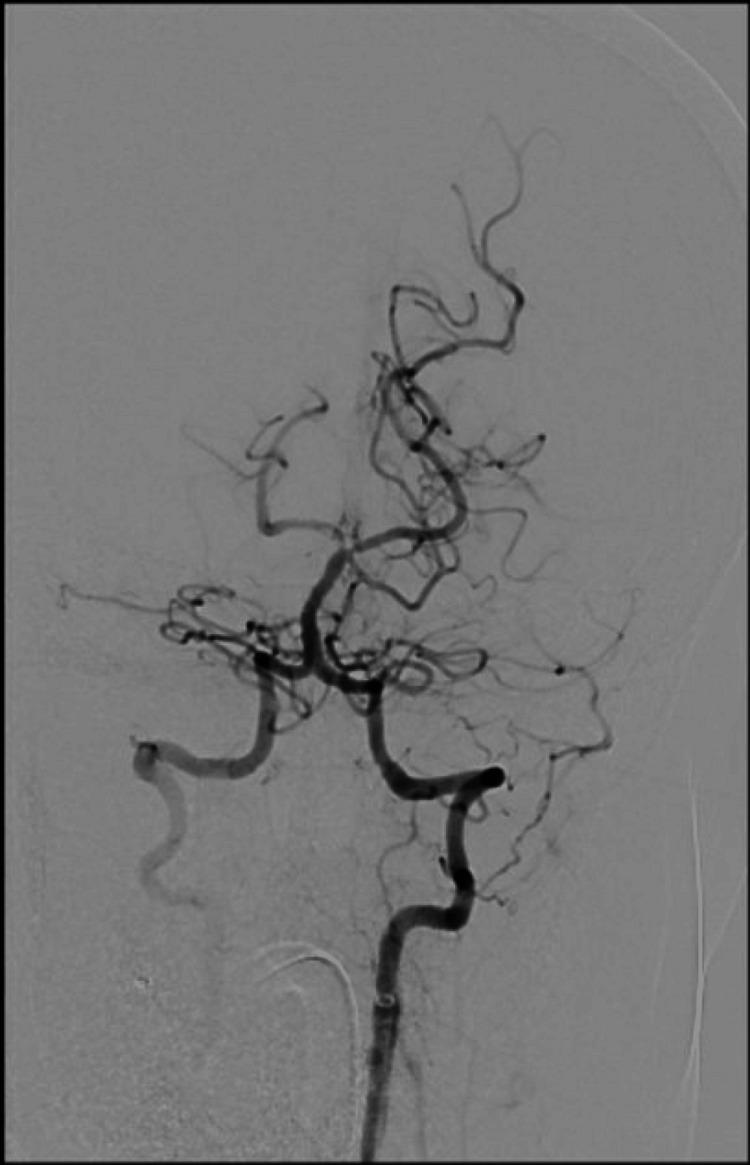

We present the case of a 40-year-old female with a previous diagnosis of unprovoked deep vein thrombosis (DVT), who had been on long-term warfarin therapy but discontinued it one month before presentation. She arrived at the emergency department following two episodes of transient loss of consciousness at work, raising concerns for a possible cerebrovascular event. Further evaluation revealed evidence of systemic embolization, as she developed acute basilar artery thrombosis and left upper limb ischemia findings consistent with multiple embolic events. Computed tomography angiography (CTA) demonstrated a mural thrombus in the thoracic aorta and occlusion of the left brachial artery. The patient received intravenous recombinant tissue plasminogen activator (rTPA), followed by successful mechanical thrombectomy of the basilar artery. She was managed with systemic anticoagulation and discharged neurologically intact. This case highlights the critical importance of maintaining anticoagulation in high-risk individuals and demonstrates the potentially life-threatening consequences of abrupt discontinuation.

摘要